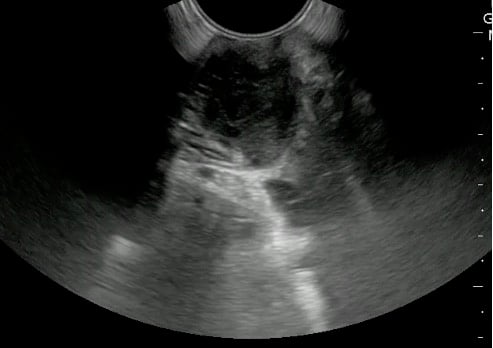

- Endocavitary probe can be used for the evaluation of tonsils.

- A 5.0 to 10.0 MHz curved array intracavitary probe is used to evaluate a suspected PTA for intraoral ultrasound. Alternatively, a high frequency linear array transducer can be used for transcervical approach, especially in children or patients with severe trismus.

- Place probe into the oral cavity over the area in question.

- The peritonsillar area should be systematically scanned in both long and short axes.

- Color Doppler should be used to identify the depth of the carotid artery and surrounding vessels.

- Alternatively, place the linear array transducer inferior and adjacent to the angle of the mandible with rotation of the head to the contralateral side. The tonsil is deep to the submandibular gland, medial to the facial vessels, and lateral to the tongue.

- Normal Tonsil

- The ovoid tonsils appear striated with hyperechoic bands and hypoechoic parenchyma, as well as lobulated margins.